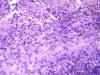

Образование левой ветви легочного ствола |

Макро фотографии к сожалению нет. Был фрагмент легочного ствола с бифуркацией, один сосуд с обычными стенками, макро без изменений, в второй неравномерно утолщен, как бы часть сосудистой стенки обычная, а часть утолщена и частично выпирала в просвет.

Эндотелизированный и реканализованный тромб трудно с чем-либо спутать. Теперь надо двигаться дальше: катамнез, причина, источник ТЭЛА и т.д. К примеру, при АФС ответ очевиден, а при "ТЭЛА" вследствие патологии ЛА - думать о сосудистом процессе.